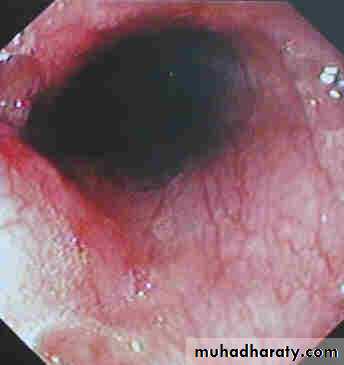

Diagnosis of Barrett’s

OGD with biopsy

Dull red of the metaplastic columnar epithelium contrasts sharply with the pale glossy normal squamous lining